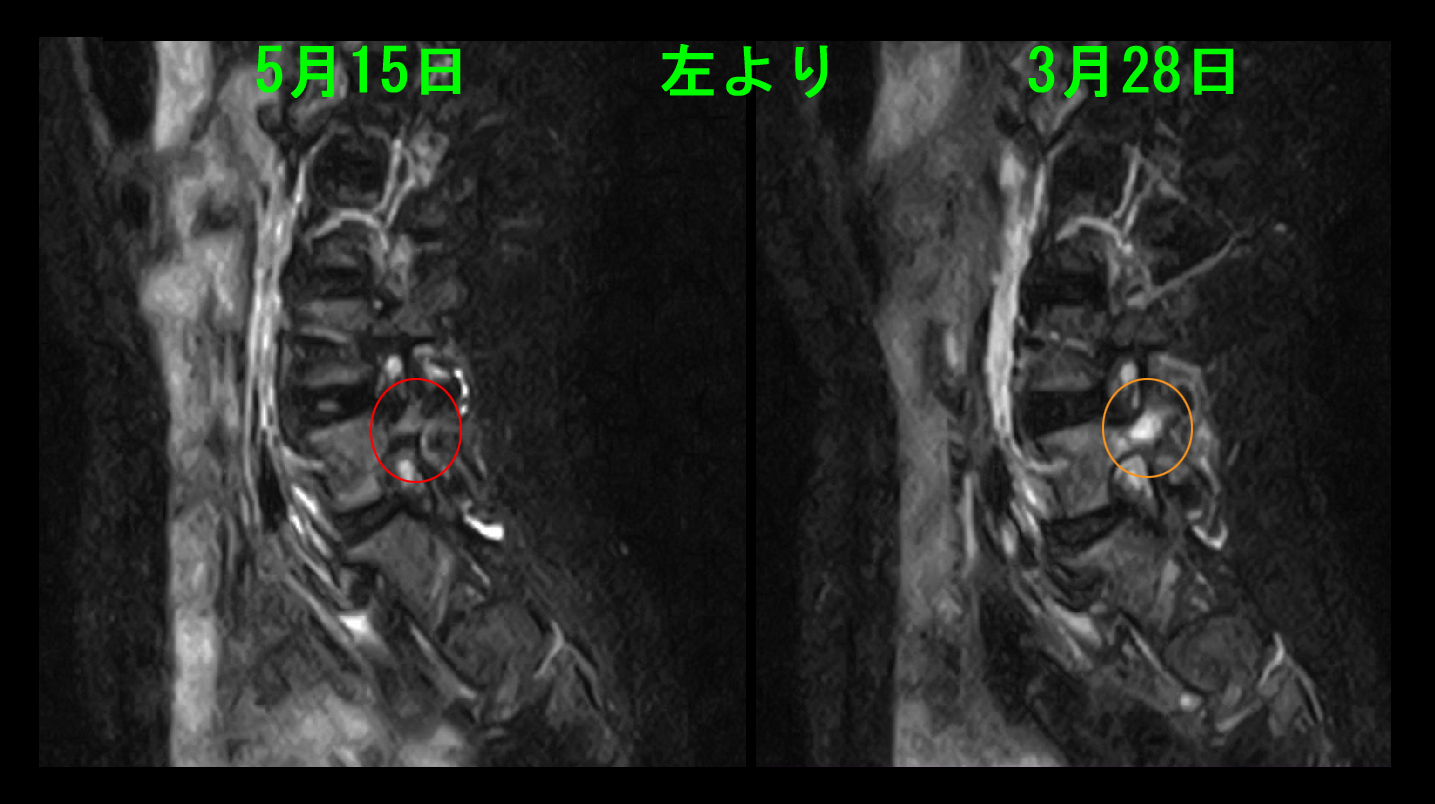

14才女 MR3.jpg

Nさんは私の分離症の治療方針にそって4週間部活と体育を休み、運動を休止した4週後の3月28日に2度目のMRI検査を行っています。しかし、分離症の所見は明瞭に軽減していませんでした。この時点での私のアドバイスは ⓐ練習を再開してみる。しかし、腰痛が再発する可能性は高い、ⓑもう4週運動を休止する。私の分離症の病態説明をしっかり理解し、運動を控えれば改善の可能性は十分あるはずだけれど、必ず治るとは約束はできない、というものでした。その後Nさんの受診はなかったので、6週後の5月10日に電話で確認すると、再検査後練習を再開したが腰痛が出たので、そこで3週間練習を休んだとのことでした。3週後に練習を再開してみると、今度は腰痛は出なかったということでした。そこで私から依頼して3度目のMRI検査を受けてもらいました。

14才女 MR4.jpg

L5の骨の損傷を示す白い高輝度所見は改善していました。